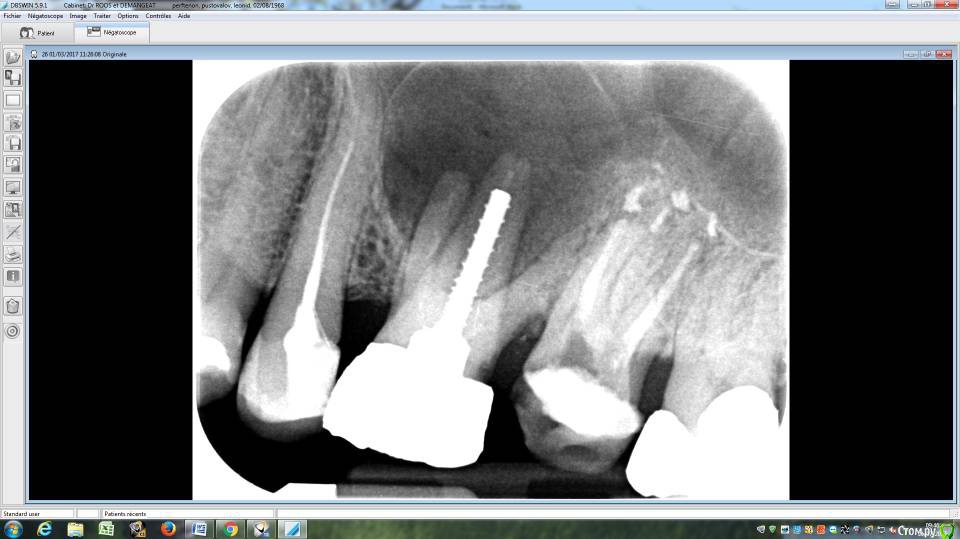

LeoRuss Опубликовано 20 февраля, 2018 Поделиться Опубликовано 20 февраля, 2018 (изменено) Здравствуйте уважаемые метры, в очередной раз обращаюсь к вам за советом.Чуть меньше года назад эндодонтическим методом в полном соответствии с вашими рекомендациями была пролечена киста 26.( http://forum.stom.ru/topic/34508-podsadka-kosti-pri-kiste-nuzhna-li-v-dannom-slucha/ ) При вскрытии зуба выявилась неприятная картина: оба титановых штифта в далеком ‘94м были завернуты мимо корневых каналов прямо в челюсть ;(Док все демонтировал, прочистил под микроскопом и каналы и дыры от штифтов и замуровал МТА : спустя 8 месяцев - 10/2017 : И вроде бы все чудесно, но пару раз за это время десна вокруг зуба воспалялась, и зуб становился более подвижным, но все проходило после 2-3-5 дневного интенсивного полоскания хлоргексидином. Три недели назад была наконец то установлена коронка на соседний 27й, десна с внутренней стороны 26ки тогда была тоже припухшей и протезист посоветовал сходить на контроль к эндодонтисту. Напросился и сходил через неделю, десна за это время еще чуть распухла (только со стороны языка), стало больно при легком нажатии на десну в районе верхушки корня ближнего к 25ке и при покачивании зуба. Док сделал снимок, сказал что все чисто и он понятия не имеет почему все надулось. Вариант удаления забраковал, сказал что по его мнению все хорошо, и можно уже ставить коронку. А вот в импланте смысла никакого, тем более что кости для него пока недостаточно, тк межкорневая область еще не дозаросла. Посоветовал терпеть и.. поставить коронку, тк нагрузка на зуб при жевании должна активировать заживление.Но жевать на этой стороне я стал почти месяц назад, сразу после установки временной коронки на 27, вот с тех пор с 26кой все хуже и хуже. За последние полнедели опухоль сильно увеличилась, и между 25/26, и в сторону нёба, дергает в ритме пульса. Появились отголоски боли в носоглотке и в заглазье.Терпеть уже плохо получается, да и смысла не вижу. Вижу два варианта:1. Удалять 26 чтоб не мучаться, с последующей имплантацией, но как быть с нехваткой кости?2. Вскрыть каналы и прочистить еще раз, но даст ли это хоть что то, да и возможно ли в принципе? В любом случае хотел бы узнать ваше мнение, спасибо ! Изменено 20 февраля, 2018 пользователем LeoRuss Ссылка на комментарий